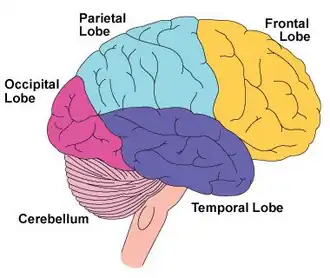

| Ilustração da vista lateral do lado direito do cérebro mostrando o lobo frontal, outros lobos do cérebro e o cerebelo | |

O distúrbio do lobo frontal, também conhecido como síndrome do lobo frontal ou disfunção do lobo frontal, é um comprometimento do lobo frontal do cérebro ocasionado por uma doença ou lesão do lobo frontal.[5] O lobo frontal desempenha um papel fundamental nas funções executivas, como motivação, planejamento, comportamento social e produção da fala. A síndrome do lobo frontal pode ser causada por uma série de condições, incluindo traumatismo craniano, tumores, doenças neurodegenerativas, distúrbios do desenvolvimento neurológico, neurocirurgia e doença cerebrovascular. O comprometimento do lobo frontal pode ser detectado pelo reconhecimento de sinais e sintomas típicos, pelo uso de testes de triagem simples e por exames neurológicos especializados.[3][6]

O lobo frontal contém o giro pré-central e o córtex motor primário e, segundo algumas convenções, o córtex orbitofrontal. Essas três áreas estão representadas nos hemisférios cerebrais esquerdo e direito. O giro pré-central ou córtex motor primário é responsável pelo planejamento, iniciação e controle dos movimentos motores finos dorsolaterais de cada hemisfério.[16] A parte dorsolateral do lobo frontal é responsável pelo planejamento, formação de estratégias e outras funções executivas. O córtex pré-frontal no hemisfério esquerdo está envolvido com a memória verbal, enquanto o córtex pré-frontal no hemisfério direito está envolvido com a memória espacial. A região do opérculo frontal esquerdo do córtex pré-frontal, ou área de Broca, é responsável pela linguagem expressiva, ou seja, pela produção da linguagem. O córtex orbitofrontal está relacionado à inibição de respostas, ao controle de impulsos e ao comportamento social.[4]